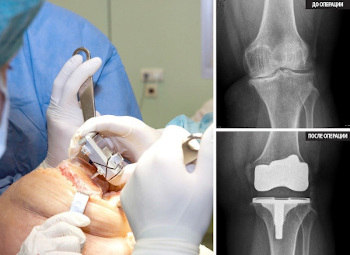

Jednstavno rečeno, bila sam šokirana! Počela sam da paničim, nisam imala novca za operaciju, a bila sam potpuno nespremna za takav poduhvat! Obim operacije je bio kosmički...i nisam bila siguran da ću takvu operaciju moći izdržati. Odlučila sam da je odbijem, i zamolila sam ljekara da mi propiše lijekove za liječenje.

Zamjena zgloba je veoma skupa i veoma ozbiljna operacija.

Endoproteza koljenskog zgloba, fotografija.